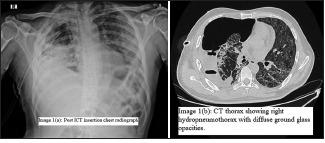

Bronchopleural fistula (BPF) is an uncommon entity in patients with coronavirus disease 2019 (COVID-19). It may arise due to various causes ranging from the disease itself to complications of treatment. If left untreated, it may increase the morbidity, hospital stay, and adversely affect the outcome. We hereby present a series of cases with a persistent pneumothorax and associated BPF due to varying etiologies. While three of our cases developed a pneumothorax while on non-invasive ventilation, other three were on oxygen therapy. One patient developed a spontaneous pyopneumothorax and septicemia and succumbed to the complications. Another patient on non-invasive ventilation died due to complications of pregnancy. The management of each case varied depending on their clinical presentation.

支气管胸膜瘘(BPF)在2019冠状病毒病(COVID-19)患者中并不常见。它可能由多种原因引起,从疾病本身到治疗并发症。如果不治疗,可能会增加发病率、延长住院时间,并对预后产生不利影响。我们在此介绍一系列因不同病因导致持续性气胸和相关BPF的病例。我们的病例中有3例在无创通气时发生气胸,另外3例接受氧疗。1例患者发生自发性脓气胸和败血症,死于并发症。另1例无创通气的患者死于妊娠并发症。每个病例的治疗方法因其临床表现而异。